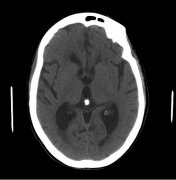

脑积水 ,是一种大脑和脊髓周围有额外的脑脊液的情况。脑脊液...

医学治疗脑积水是用来推迟手术干预。它可能用于早产儿出血性...